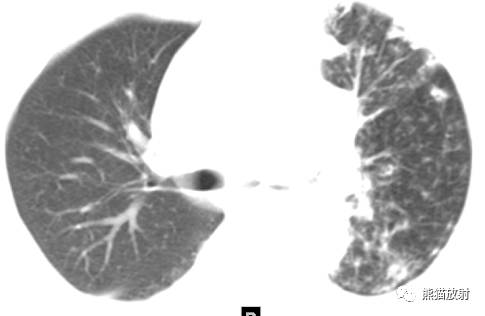

首诊(左图):容易只诊断为曲霉菌感染,空洞内移动的霉菌球的表现很抢眼,但容易忽略洞壁局部增厚并与胸膜关系密切(大箭),左下肺门可见增大淋巴结(小箭); 医学百科网 | YxBaike.Com

四个月后复查(右图):空洞增大,洞壁明显不规则增厚,左下肺门淋巴结明显肿大;已经足以证明这是一例左下肺肺癌并曲霉菌感染,发生在癌性空洞内的寄生型肺曲霉病(肺曲霉球)。